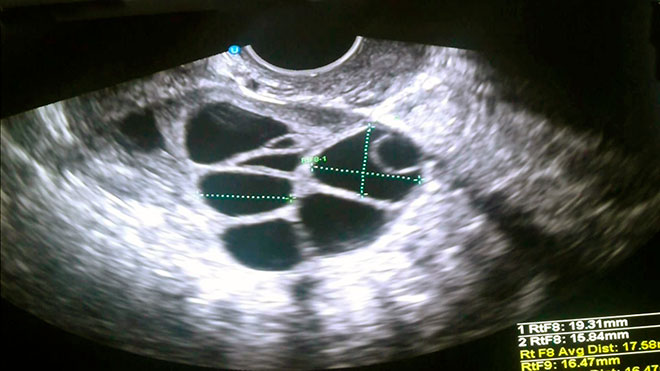

Режим инъекций гормонов называют протоколом или схемой стимуляции, и для каждой пациентки он подбирается индивидуально. При помощи УЗИ отслеживают рост фолликулов яичников, и когда они достигают определенного размера, яйцеклетки извлекают, аспирируя содержимое фолликулов.

Оптимальное количество извлеченных ооцитов – от 8 до 12 единиц. Оплодотворяют по возможности все здоровые клетки. Но сколько из них перенесут процедуру удачно – спрогнозировать сложно, в целом, 50%-90% зародышей получаются жизнеспособными.